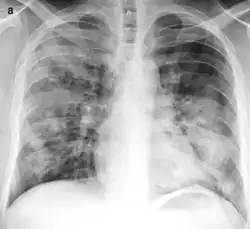

| Typical distribution of lobar pneumonia (left in image) and bronchopneumonia (right in image) | |

On gross pathology there are typically multiple foci of consolidation present in the basal lobes of the human lung, often bilateral. These lesions are 2–4 cm in diameter, grey-yellow, dry, often centered on a bronchiole, poorly delimited, and with the tendency to confluence, especially in children.